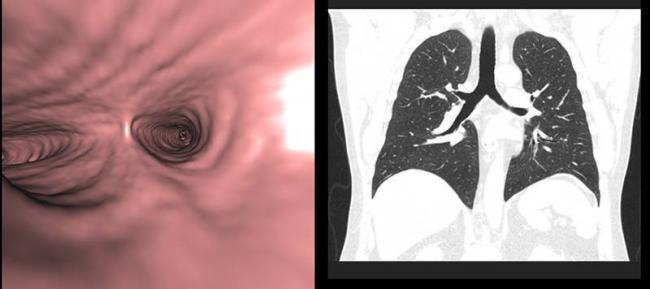

Суть исследования

Томография является высокоинформативным методом послойного исследования тканей и внутренних органов, позволяющим увидеть на снимке даже самые мелкие детали – хорошо визуализируются очаги размером в 1–2 мм. Она относится к рентгенологическим исследованиям, когда изображение формируется путем просвечивания каждого среза, толщина и направление которого может регулироваться, исходя из характера легочной патологии.

Проходя сквозь ткани различной плотности, излучение ослабевает, а степень его изменения регистрируется чувствительными сенсорами. Полученная информация анализируется компьютером и нередко представляется в виде трехмерной картинки. Томографическое исследование легких может выполняться в нескольких режимах:

- Непрерывный – делают все срезы органа.

- Дискретная – интервал между срезами увеличен.

- Прицельная – анализируют лишь определенный участок органа.

Сравнивая КТ легких при пневмонии с обычным рентгенологическим исследованием, преимущества томографии очевидны: более высокая чувствительность и точность. Она позволяет обнаружить наиболее мелкие детали патологического процесса, не давая усомниться в диагнозе. Однако исследование не так доступно и сопряжено с более существенной лучевой нагрузкой на пациента.